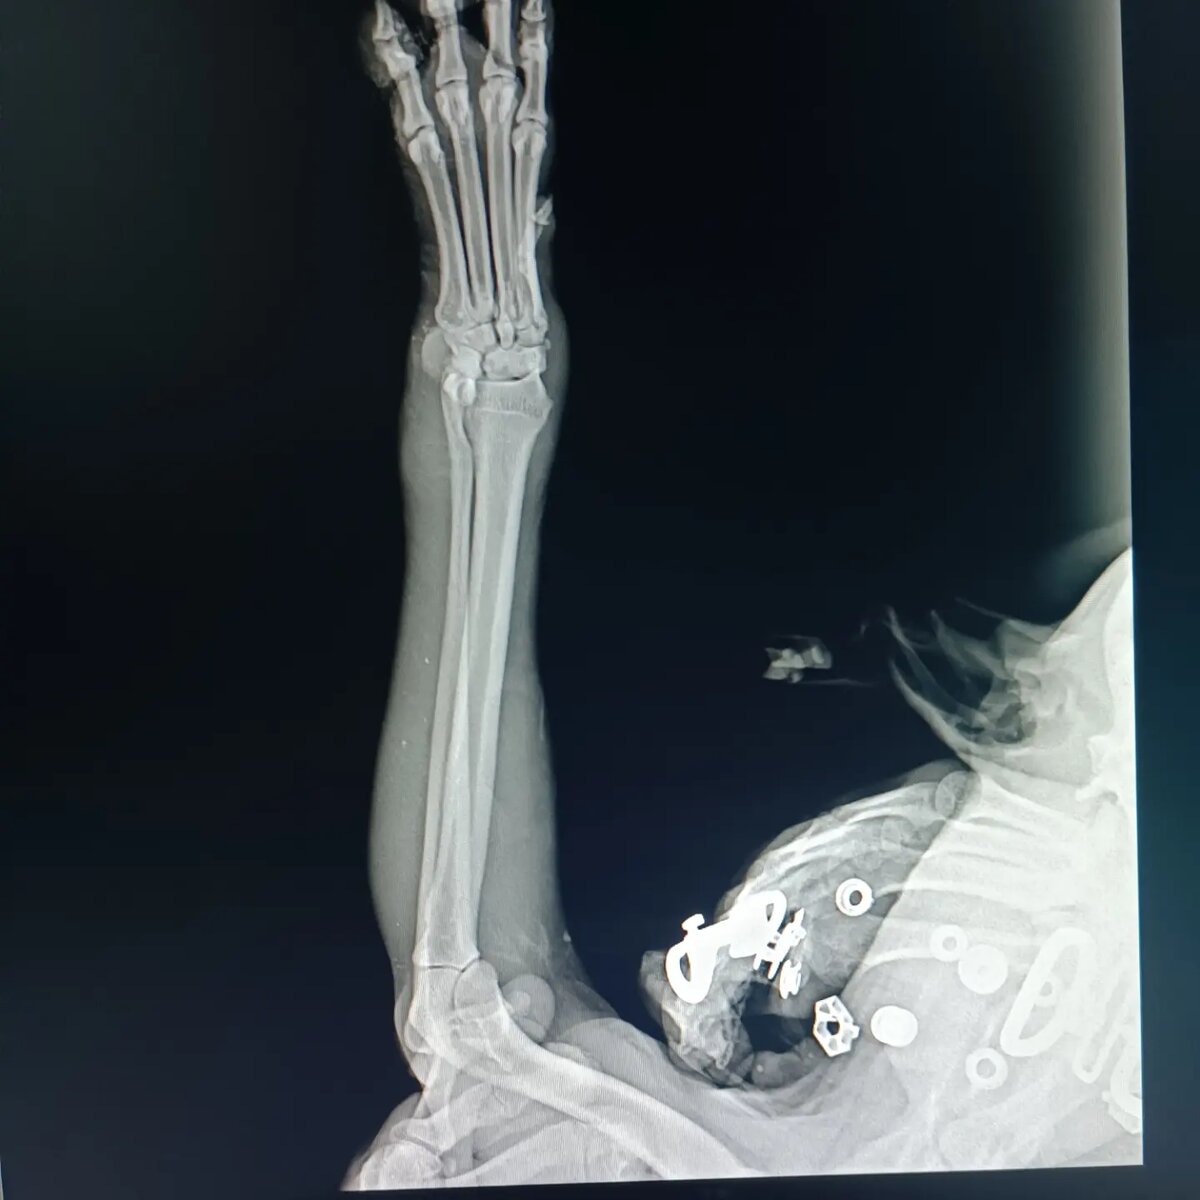

Теперь его зовут Тошка, и он прошёл все круги ада! ❌

Не знаю выбросил его кто-то или всю жизнь рос на улице.. Попал в отлов, навсегда остался инвалидом с нервными тиками, после чумы..

Вчера на глазах у людей его сбила машина! Всю ночь он сидел и плакал, никто не хотел помочь ему...

По рентгену нет переломов, но лапа в ужасном состоянии...

Чуть позже посмотрит хирург, нет ли повреждения нерва...

Будем надеяться, что нет, иначе только ампутация...

Тошка в стационаре. Это опять огромные расходы.. .. Денег сейчас совсем нет.. А в клинике надо оставить хоть какой-то аванс.